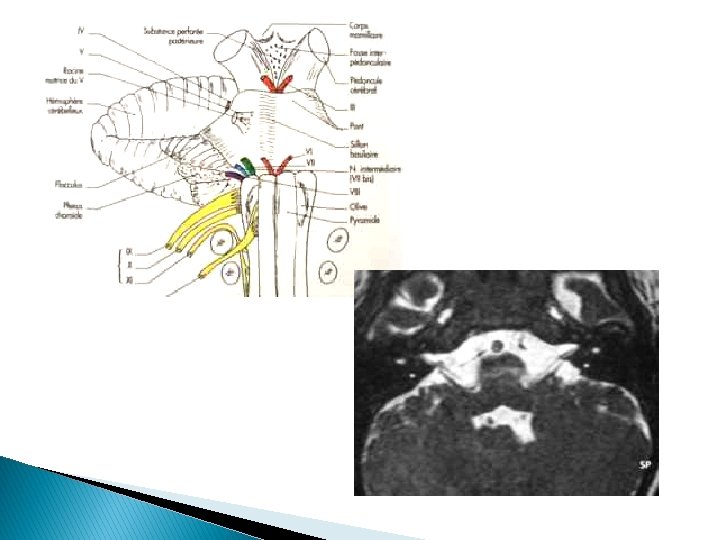

� PFP : déficit du territoire facial musculaire supérieur → atteinte NF homolatéral sur son trajet entre l’origine nucléaire et la terminaison intraparotidienne

NF NVS Cervelet NC NVI